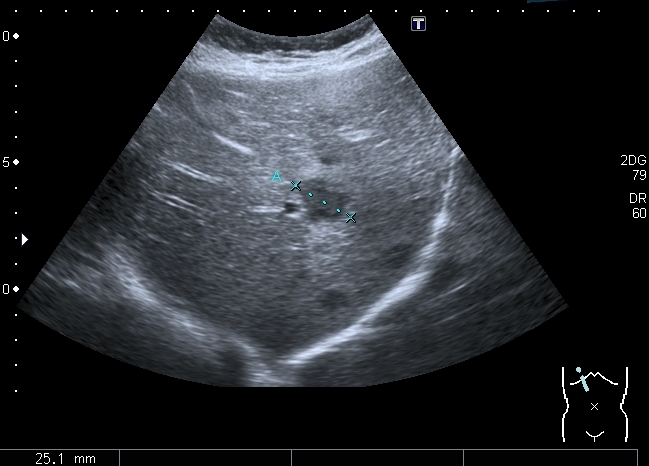

Девочка 13 лет, в течение 2-х недель температура до 38, СОЭ - 40 мм\ч, СРБ - 30.

На УЗИ: Учитывая клинику, лабораторные данные поставил гистиоцитарную инфильтрацию печени и селезёнки при генерализованной инфекции. Несколько раз встречался со схожими случаями, на фоне антибиотикотерапии изменения уходили. Но в данном случае девочка уже получала антибиотики в течение недели, на этом фоне не получено ни клинического , ни лабораторного улучшения, а на УЗИ очаги стали больше. Нужно ли расширять дифференциально -диагностический ряд? Ваши мнения

Имхо, по УЗ-семиотике - множественные небольшие абсцессы.

Из -за того , как назвать данные изменения у нас в больнице постоянно возникают споры между педиатрами и хирургами, а крайние - мы. Если мы в своём заключении упомянём слово "абсцесс" - девочку сразу же переведут в хирургическое отделение: абсцесс= гной, где гной - там разрез. Весь вопрос в том , что гноя в этих очагах нет и хирурги категорически отказываются участвовать в лечении данного заболевания, скорее это инфильтраты, или по лекции С. И. Пиманова - гистиоцитоз печени и селезёнки. Упомянув данное слово , мы ввергаем педиатров в панику, т. к. у них возникает ассоциация с гистиоцитозом X, хотя это несолько из другой оперы.KapustinSV писал(а):Имхо, по УЗ-семиотике - множественные небольшие абсцессы.

Мне нравится информация по данной патологии из видаровского "Клинического руководства по ультразвуковой диагностике в педатрии". Там данные изменения носят название очаговых поражений инфекционной этиологии (иерсиниоз, псевдотуберкулёз, токсокароз, хламидиоз и др.). Но инфекционисты, проведя ИФА с очень скудным набором диагностикумов и получив отрицательный результат, так же говорят, что это "не их".